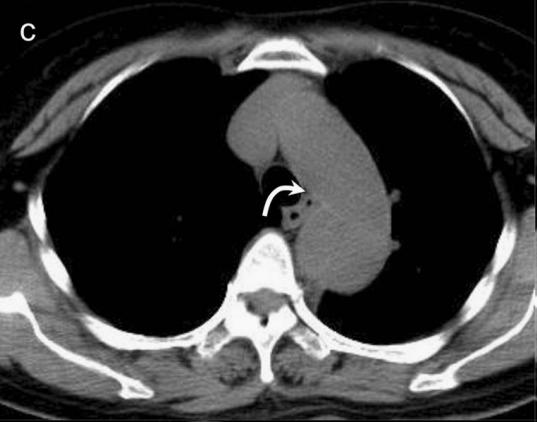

下图的胸部CT平扫,基本上大约肯定可以看到一条线样阴影,将主动脉一分为二!

下面的CT平扫,隐隐约约基本肯定看到主动脉夹层了!

不行,你再看看,越看越像!